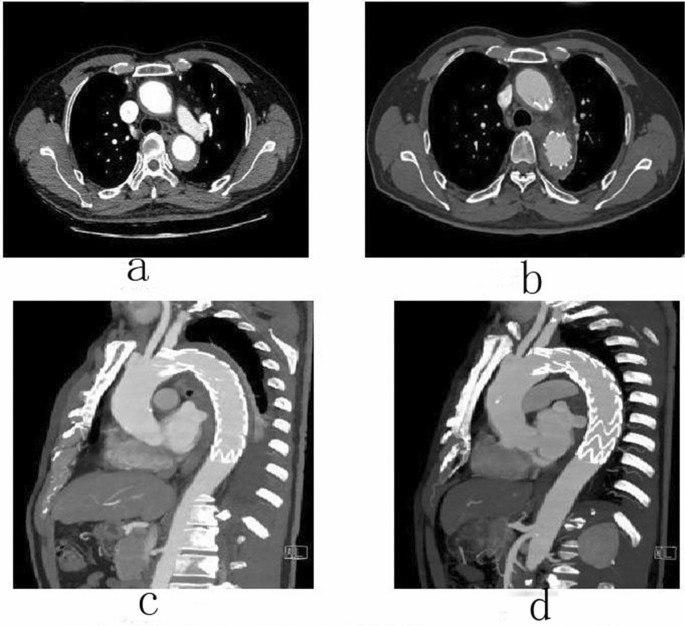

Follow-up

Male, 62 years old, admitted to hospital for “repetition of chest and back pain for 9 h”. Diagnosis: Standford A IMH TEVAR. CTA of the patient in different periods: (a) Admission; (b) 5 days after surgery; (c) 5 days after surgery; (d) 3 months after surgery.